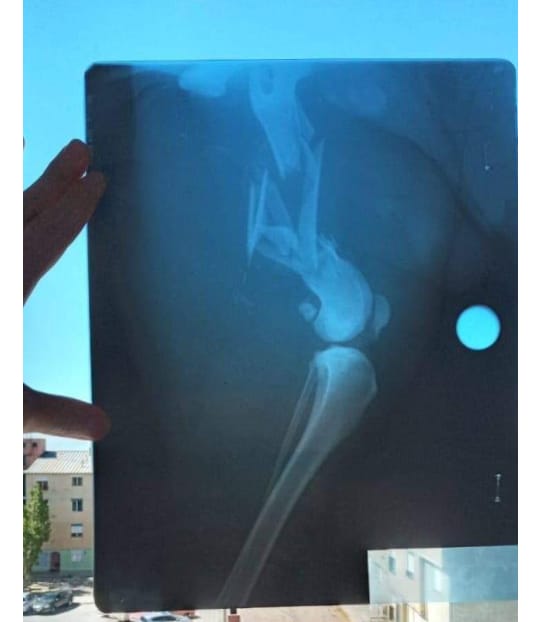

La perra de nombre Miel, se encuentra con una grave fractura de fémur, por la que debe ser intervenida quirúrgicamente, la operación cuesta 13 mil pesos.

De no ser intervenida, Miel perderá su pierna.